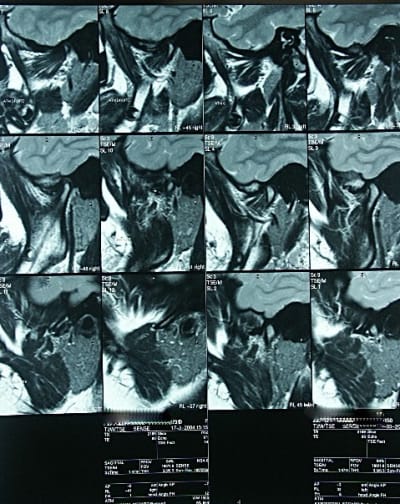

Compte rendu de l'IRM des ATM:

- protocole: séquences dynamiques en sagittales droite et gauche, et réalisation de séquences sagittales en T2.

- résultat: sur les séquences T2, il n'y a pas dépanchement intra-articulaire. Le ménisque gauche est correctement situé et sa mobilité est satisfaisante lors de l'ouverture de la bouche. A droite, il semble exister une désinsertion postérieure du ménisque qui se luxe antérieurement, particuliérement lors de l'ouverture de la bouche.

- Conclusion: la subluxation antérieure de la bouche ouverte se fait normalement: la ménisque gauche présente une cinétique normale, tandis que le ménisque droit semble présenter une luxation antérieure.

Les examens ont été prescrits par l'ortho. Je ne sais pas si l'IRM était indispensable pour confirmer le diagnostic d'antéposition discale.

Sur cervicales:je considère que la posture n'est pas au top,mais bon...

Sur le 5ème et 8ème cliché,je devine une postériorisation du condyle,donnant une compression de la zône bilaminaire,qui a l'habitude de générer beaucoup de symptômes.

Le reste est ininterprètable pour moi sur ces retransmissions,atm et ménisques très flous.